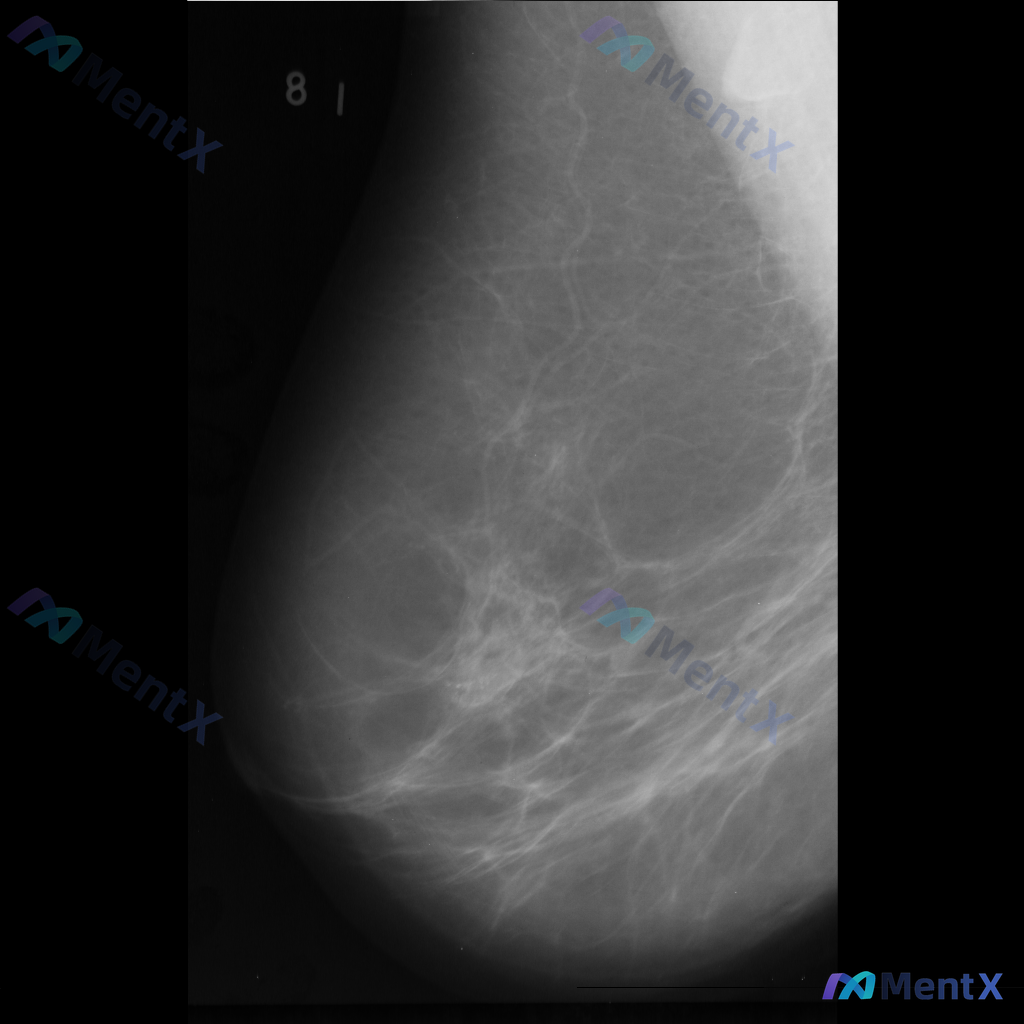

整理到一组乳腺钼靶影像的资料,分享给大家讨论: - 背景:不均匀致密型乳腺(BI-RADS C类) - 主要异常: 1. 乳腺下象限靠近乳头乳晕区,见两个大小不一的圆形/卵圆形高密度影,还有一个较小的类圆形高密度影,密度高于周围腺体,边缘相对清晰但略显模糊; 2. 上述高密度影周围的乳腺下象限,腺体...